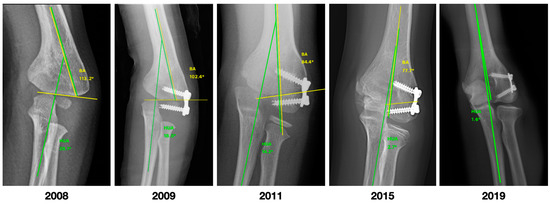

| CA | −20 (−18 to −26) | −6 (−4 to −9) | −16 (−18 to −9) | <0.001 |

| HUA | −19 (−15 to −29) | −8 (−1 to −10) | −16 (−19 to −12) | <0.001 |

| BA | 90 (87 to 100) | 81 (76 to 83) | −11 (−17 to −7) | <0.001 |

| SCA | 29.8 (24.3 to 36.2) | 38.5 (38.1 to 40) | 7.5 (3.3 to 13.8) | <0.001 |

| LCHA | 61.6 (54 to 64.1) | 56.7 (54.6 to 57.3) | −4.8 (−6.8 to 0.6) | 0.018 |